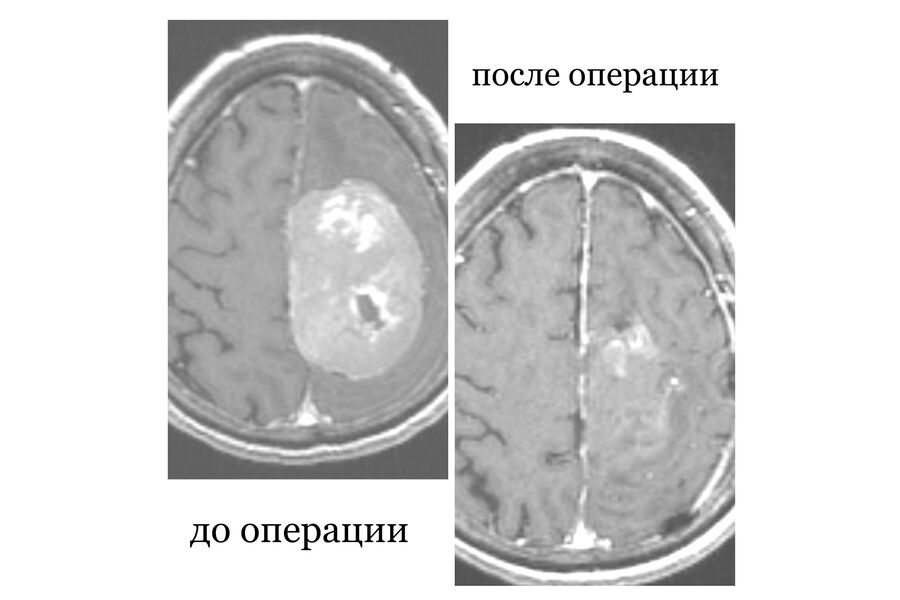

В Республиканской клинической больнице Бурятии медики прооперировали пациентку с опухолью головного мозга, женщина шесть лет отказывалась от хирургического вмешательства. Об этом сообщает пресс-служба медицинского учреждения.

76-летняя пенсионерка поступила в больницу с жалобами на нарушение речи и слабость в конечностях. Врачи установили, что еще в 2018 году у пожилой женщины была диагностирована опухоль головного мозга, однако тогда пациентка отказалась от операции и не стала продолжать лечение.

«При поступлении пациентка уже не могла двигаться, была нарушена речь, сознание спутанное. Мы сразу же приступили к противоотечной терапии. Переговорили с родственниками и они, наконец-то дали свое согласие на операцию», — сообщил нейрохирург республиканской клинической больницы Булат Цыбиков.

Хирургическое вмешательство прошло успешно, спустя неделю после операции пенсионерку выписали на амбулаторное лечение.